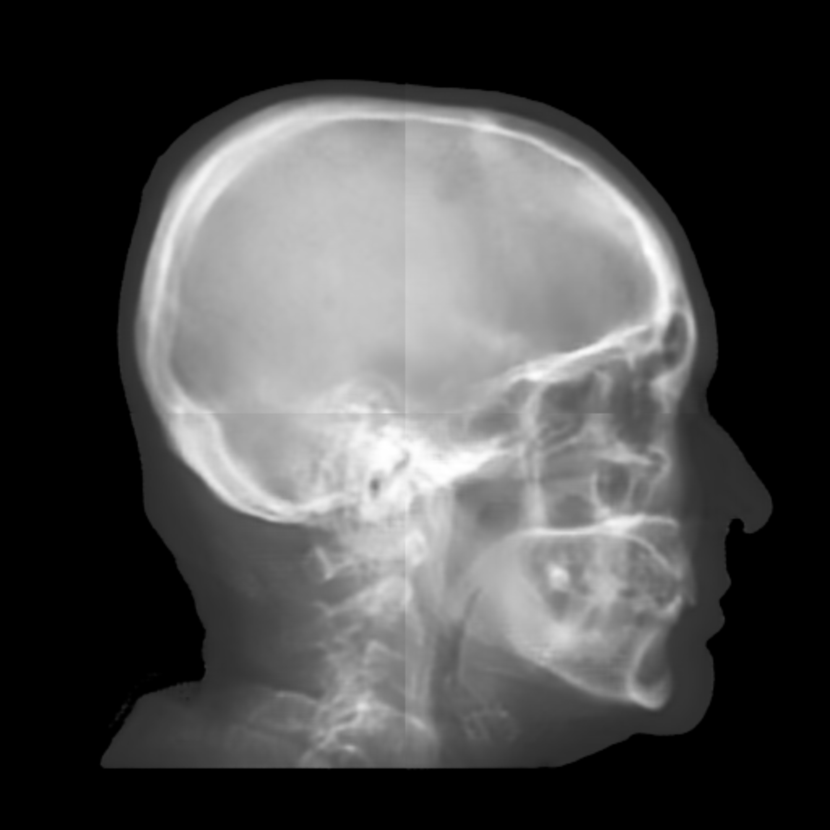

Refer to caption

(a) Real cephalogram

(b) Synthetic cephalogram

(c) Plot of samples and sigmoid curves

Fig. 2: Image contrast difference between real conventional cephalograms and RayCast synthetic cephalograms: (a) a real cephalogram example; (b) a RayCast synthetic cephalogram example; (c) the plot of samples between RayCast synthetic cephalograms and real cephalograms with an original sigmoid curve (red) and our proposed modified sigmoid curve (blue).

In Fig. 2, one real conventional cephalogram example and one example of 𝒈𝒈\boldsymbol{g} are displayed, where evident image contrast difference between these two images is observed. It is because the X-ray films used in conventional cephalograms have the special nonlinear optical property that the characteristic curve between optical density and logarithmized X-ray exposure has a sigmoid-like shape [42]. According to the Lambert-Beer law, the logarithmized X-ray exposure is equivalent to the attenuation integral. It indicates that the intensity relation between the desired cephalogram and the attenuation integral image 𝒈𝒈\boldsymbol{g} should also exhibit a sigmoid-like curve. Therefore, to make the image contrast of synthetic cephalograms similar to conventional cephalograms, a sigmoid intensity transform is necessary.